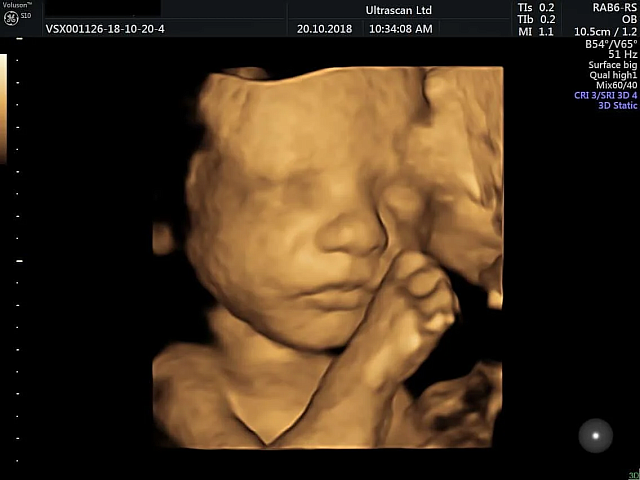

Τα έμβρυα παίρνουν πιο «γελαστό πρόσωπο» στη μήτρα όταν εκτίθενται στη γεύση των καρότων που καταναλώνει η μητέρα τους και «πιο κλαμένη έκφραση» όταν εκτίθενται στη λαχανίδα (κέιλ), σύμφωνα με μελέτη που δημοσιεύθηκε στο περιοδικό Psychological Science.

Η μελέτη εξέτασε τα υγιή έμβρυα 100 γυναικών ηλικίας μεταξύ 18 και 40 ετών, οι οποίες ήταν μεταξύ 32 και 36 εβδομάδων κύησης στη βορειοανατολική Αγγλία.

Οι 35 γυναίκες μπήκαν σε μια πειραματική ομάδα που κατανάλωσε μια κάψουλα οργανικού κέιλ, 35 μπήκαν σε μια ομάδα που πήρε μια κάψουλα καρότου και 30 μπήκαν σε μια ομάδα ελέγχου που δεν εκτέθηκε σε καμία από τις δύο γεύσεις.

Από τις συμμετέχουσες ζητήθηκε να μην καταναλώσουν κανένα τρόφιμο ή ποτό με γεύση μία ώρα πριν τον υπέρηχο. Οι μητέρες επίσης δεν έφαγαν ούτε ήπιαν κάτι που να περιέχει καρότο ή λάχανο την ημέρα των υπερήχων για να βεβαιωθούν ότι δεν θα επηρέαζε τα αποτελέσματα.

Αφού περίμεναν 20 λεπτά μετά την κατανάλωση, οι γυναίκες υποβλήθηκαν σε 4D υπερηχογραφήματα, τα οποία συγκρίθηκαν με 2D εικόνες των εμβρύων.